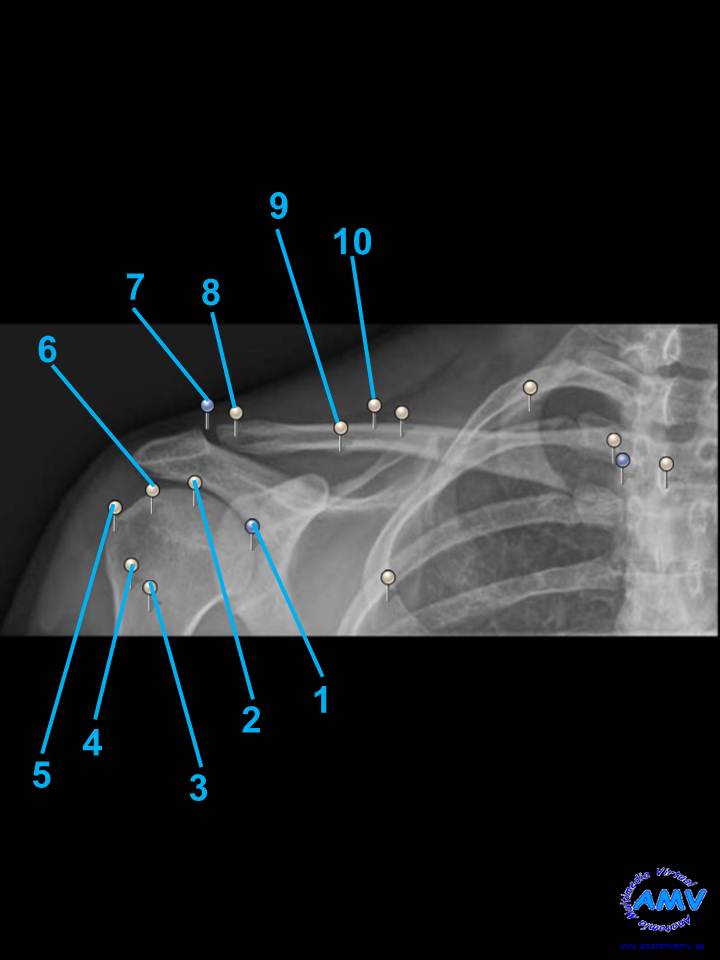

rx_ms_02.jpgIndique que estructura se señala con el número correspondiente:

El nº 1 señala .

El nº 2 señala .

El nº 3 señala .

El nº 4 señala .

El nº 5 señala .

El nº 6 señala .

El nº 7 señala .

El nº 8 señala .

El nº 9 señala .

El nº 10 señala .